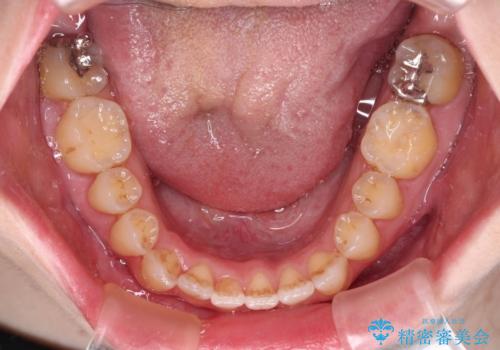

オープンバイトと前歯のデコボコをインビザライン矯正で解消

オープンバイトは舌の突出癖により誘発され、治療後も突出癖が残っている容易に後戻りしてしまいます。

治療期間を短縮するためにも、舌突出癖の改善が極めて重要となります。